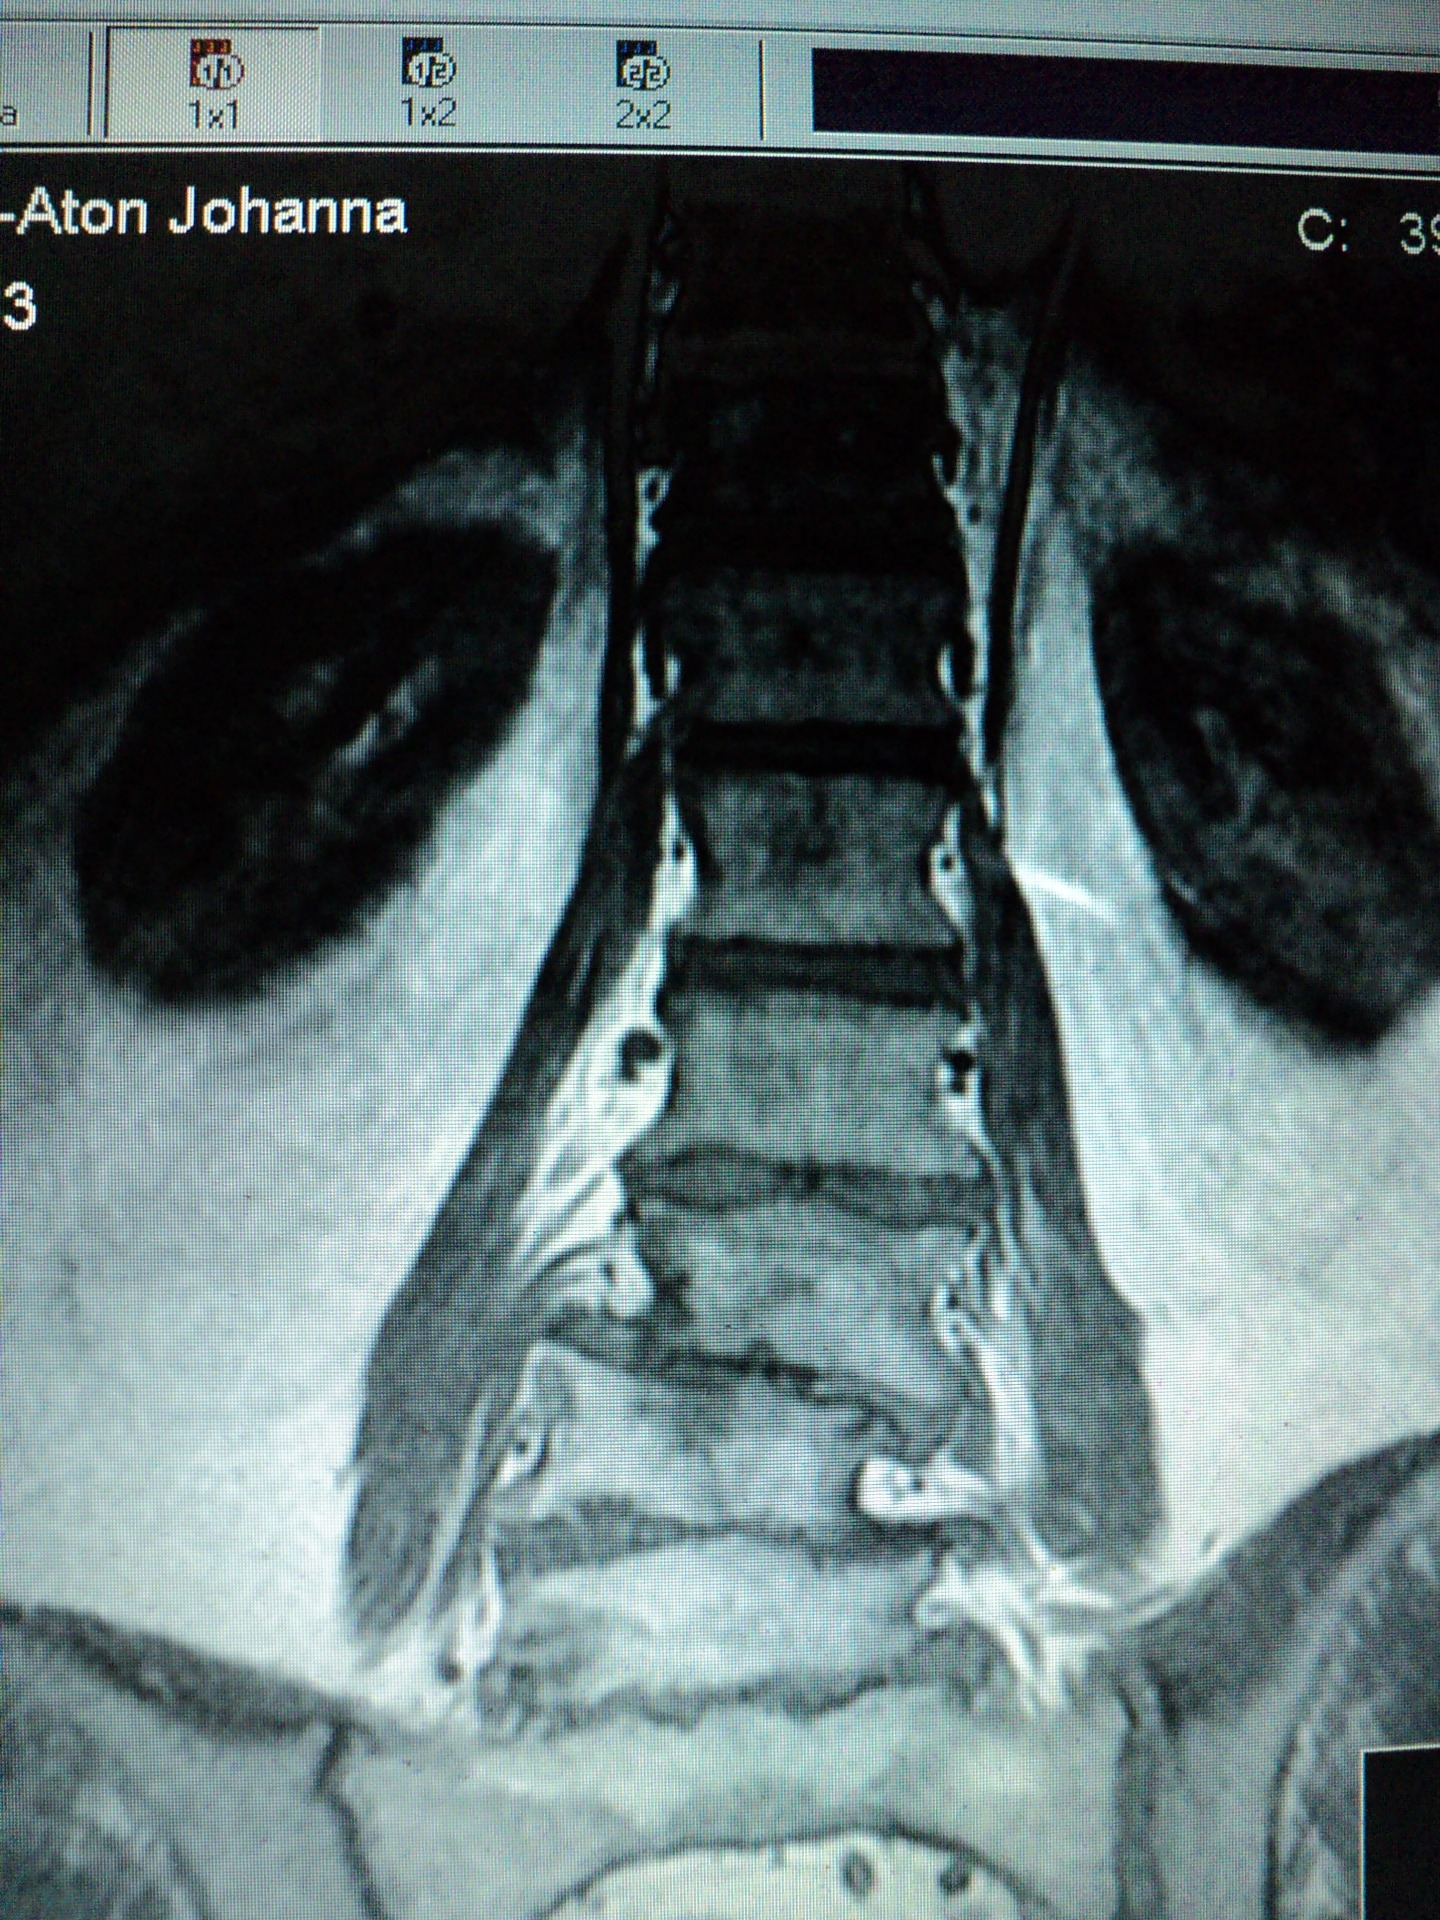

(Tämä kuva selästäni on vuodelta 2003.)

UNIVIESTI: "TULEMME POISTAMAAN SINULTA 10 CM SELÄSTÄ."

LYHENTYMINENKIN ON ERITTÄIN EPÄMUKAVAA.

ON IHME, ETTÄ OLEN PYSTYNYT KÄVELEMÄÄN NÄINKIN KAUAN JA ETTÄ "PUTKISTO" ON TOIMINUT...

Tämä kuva selästäni on vuodelta 2014. Näin sen vasta 2017, sen JÄLKEEN, kun olin auttanut kuolevaa isääni muuttamaan Hankasalmella.

Kotilääkärini yritti kolme kertaa tuputtaa minulle psyykenlääkkeitä, kun itkin hän luonaan. Kieltäydyin niistä. Kotilääkäri itse ITKI, kun hän näki magneettikamerakuvat! Pian hän jäi eläkkeelle.